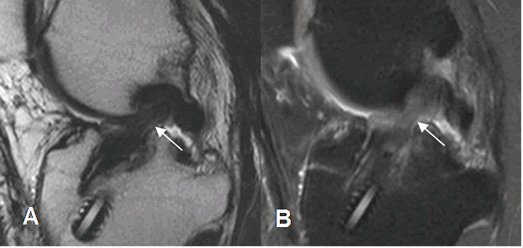

Fig 142. Ruptura del injerto.

A: RM sagital en T2. Pérdida de la tensión y orientación en las fibras del injerto, sospechando su ruptura.

B: ArtroRM sagital en STIR. Se confirma la ruptura de injerto, con interrupción de sus fibras.